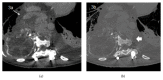

Giant cell tumor of bone (GCT) is a rare, locally aggressive neoplasm characterized by the presence of giant cells with osteoclast activity. Its biology involves the overexpression of the Receptor Activator of Nuclear Factor kB Ligand (RANKL) by osteoclast-like giant cells and tumor stromal cells, which has been shown to be an actionable target in this disease. In cases amenable to surgical resection, very few therapeutic options were available until the recent demonstration of significant activity of the anti-RANK-ligand monoclonal antibody denosumab. Here we present a case of a patient with advanced GCT arising in the spine, recurring after multiple resections and embolization. Following initiation of denosumab, which resulted in unequivocal clinical improvement, computed tomography of the chest done for reassessment purposes revealed an intratumoral pseudoaneurysm by erosion of the aorta, further corrected by endovascular approach and stent placement. Patient had an unremarkable recovery from the procedure and continued benefit from therapy with denosumab and remains on treatment 24 months after the first dose.